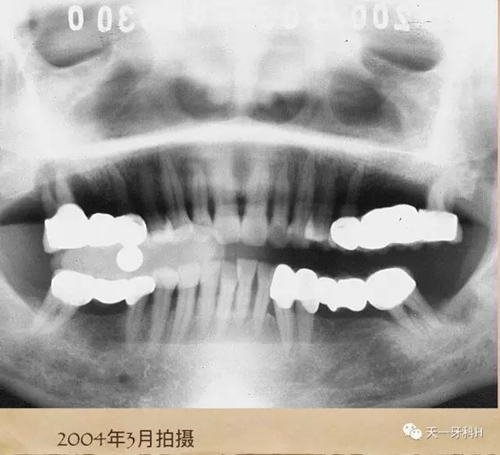

2004年3月27日17:

17牙槽骨已經(jīng)破壞到了根尖,這樣的牙齒的松動度已經(jīng)到達了三度,17的每一次搖動都會造成固定橋另一端的基牙15的搖動,久而久之15的牙槽骨也被破壞了,此時應該盡早拆除固定橋。

很多患者問我為什么反對牙周病患者做烤瓷連橋,這就是烤瓷橋?qū)е卵啦酃瞧骗h(huán)的一個例子,我在2004年收集的證據(jù),就是為了今天向你們說明這個問題,我追蹤觀察了十三年,我不是研究者,我僅僅是一個臨床醫(yī)生,我不能給你們結(jié)論性的東西,我只能給你們實例,我記錄下來的實例。